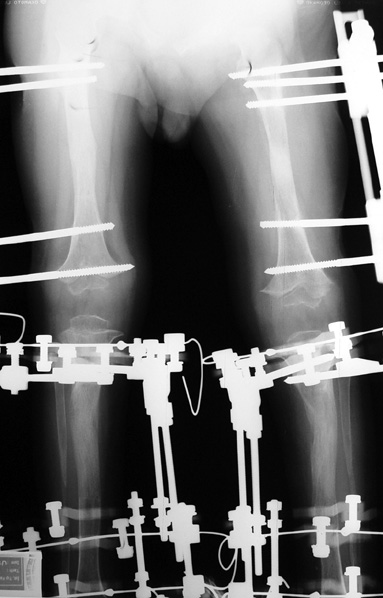

12-14 yaşları arasında Her iki tibiada toplam 10-15cm boy uzatma (iki seviyeli uzatma) Proksimal tibianın varus deformitesini proksimal osteotomi ile düzeltilmesi Distal tibianın varus deformitesi distal osteotomi ile düzeltmesi Distal tibianın varus deformitesi distal osteotomi ile düzeltmesi Boy uzatmanın sonunda lateral kollateral ligamentin gerilmesi Ortalama eksternal fiksasyon tedavi süresi = 8-10 ay

13-15 yaşlar arasında Her iki humerusu (kol) 8-12 cm boy uzatma Dirseklerin fleksiyon deformitesini düzeltme Ortalama eksternal fiksasyon tedavi süresi = 6-8 ay Alt uzuvların iki uzatması arasında üst uzuvlar uzatılarak alt uzuvların dinlenmesi sağlanmış olur. Cihaz çıkartıldıktan sonra en erken ikinci uzatmaya başlama süresi 6 aydır. Bilateral femoral uzatmalarda uzatma fazı sırasında hastanın yürümesi mümkün değildir. Ayakta durmaya sadece hasta transferi sırasında izin verilir. Uzatma fazında ambulasyona sadece tekerlekli sandalye ile izin verilir. Konsolidasyon fazında ise tedrici olarak daha fazla yük verilmesine ve cihazın çıkmasına yakın serbest yürümeye izin verilir. Bilateral tibial uzatmalarda ilk günden itibaren yürüteç veya koltuk değneği ile hastanın yük vermesine izin verilir. Uzun gezintiler tekerlekli sandalye ile yapılmalıdır. Bilateral humeral uzatmalarda hemen hemen hiçbir aktivite kısıtlaması yoktur. Uzatma süresince her iki haftada bir yapılan takiplerde kantitatif duyusal sinir testleri doktor tarafından yapılmalıdır. Bu gelişmekte olan sinir sorunlarını klinik olarak ortaya çıkmadan yakalamaya izin verir. Femoral ve humeral uzatmalarda çok nadir görülmesine rağmen tedavi edilmedikleri durumda düşük ayağa (ayağı yukarı çeken kasları innerve eden sinirin felci) neden olabilirler. Eğer erken tespit edilir ve uzatmanın hızı azaltılırsa, sinir problemi genellikle kendiliğinden düzelir ve uzatmaya düşük hızda devam edilir. Uzatmada yavaşlamaya rağmen sinir problemi devam ederse sinirin cerrahi olarak gevşetilmesi gerekir. Bu işlem 1cm’ lik bir kesi ile yapılabilen ve hastanede bir gece kalmayı gerektiren küçük bir işlemdir. Bu ameliyat el bileğinde sinir sıkışması (karpal tünel sendromu) için yapılana benzerdir.